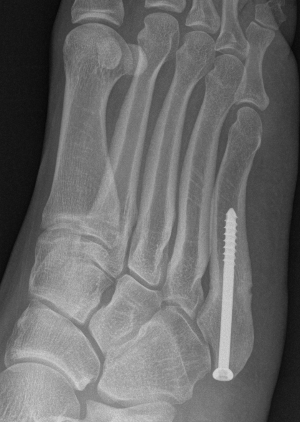

Displaced fracture Nonunion

Intramedullary Screw

Screw fixation Zone 2 nonunion

Screw fixation Zone 3 nonunion